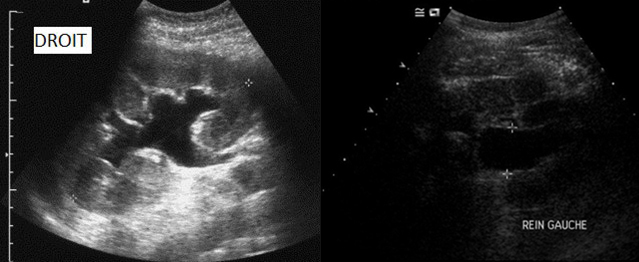

Le patient est réhospitalisé en urgence devant une altération de l’état général, des vomissements et de la fièvre à 38,9 °C. Les douleurs osseuses sont réapparues depuis quelques semaines et sont mal contrôlées par les antalgiques. Le patient réalise quotidiennement ses auto-sondages sans difficulté et la vessie est vide à l’examen clinique, mais il existe une sensibilité des fosses lombaires bilatérale à la palpation. Le bilan biologique retrouve : 22 000 GB, urée 25 mmol/L, créatininémie 600 µmol/L, K 4,6, calcémie totale corrigée 2,30 mmol/L. Sa créatininémie réalisée il y a 1 an était normale (créatininémie de base : 85 µmol/L). Les plaquettes et le TP sont normaux.

Dans le contexte de progression tumorale avec altération de l’état général et majoration de douleurs osseuses métastatiques, il faut suspecter une progression loco-régionale du cancer de prostate avec envahissement du trigone et des 2 méats urétéraux, qui peut expliquer une insuffisance rénale obstructive compliquée de pyélonéphrite obstructive.

L’obstacle n’est pas sous-vésical par compression de l’urètre car le patient s’auto-sonde sans difficulté et la vessie est vide.

Une insuffisance rénale obstructive n’est possible que lorsqu’il existe une obstruction urétérale bilatérale, ce qui est le cas lors d’une rétention d’urine ou en cas d’envahissement du trigone et des 2 méats urétéraux par une maladie tumorale (prostatique, vésicale, cancer du col ou de l’endomètre…). Il peut également exister de rares cas de compression urétérale abdominale par adénopathies bilatérales ou exceptionnellement de calculs urétéraux bilatéraux.

Vous réalisez une échographie aux urgences :

Question 15 - Dans ce contexte, vous proposez (une ou plusieurs réponses exactes) :

L’évolution loco-régionale des cancers de prostate et de vessie aboutit souvent à des tableaux de rétention d’urine, de caillotage vésical et/ou d’envahissement du trigone et des méats urétéraux avec insuffisance rénale obstructive +/- pyélonéphrite par dilatation bilatérale des cavités pyélo-calicielles. Il s’agit alors d’un tableau urgent nécessitant une antibiothérapie en cas de fièvre/surinfection et un drainage des cavités rénales par néphrostomies bilatérales ou pose de sondes JJ bilatérales si les méats sont visualisés en cystoscopie. En cas de pose de néphrostomies 1re, on pourra tenter dans un second temps une descente de JJ après repérage des méats urétéraux, afin de proposer un drainage interne des urines.

Les soins de confort doivent être mis en place et la pose de néphrostomie bilatérale peut largement entraver la qualité de vie et devra être discutée avec le patient et sa famille ainsi qu’une éventuelle radiothérapie pelvienne en cas de symptomatologie douloureuse ou hémorragique.